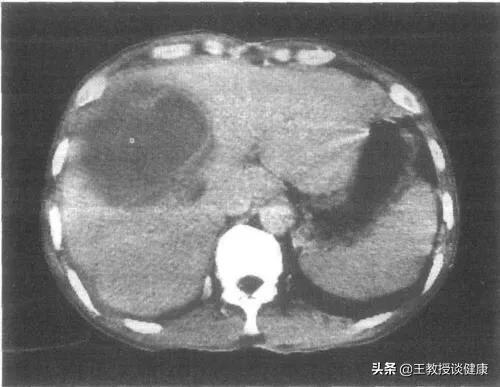

CT所见肝右叶肝脓肿明显液化影像